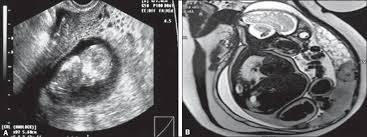

Pdf Ultrasound And Mri Findings In Gestational Trophoblastic Disease Gtd Learning Objectives